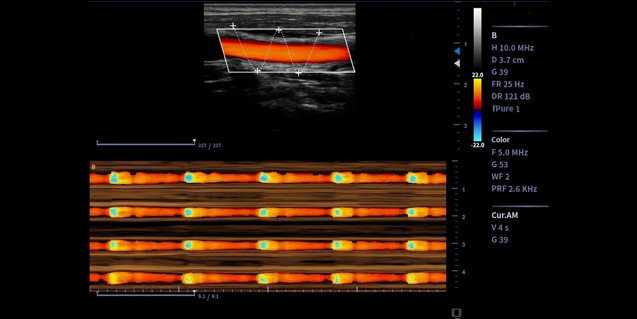

高频率成像,更适用于婴幼儿小器官,血管检测

微血流成像

传统